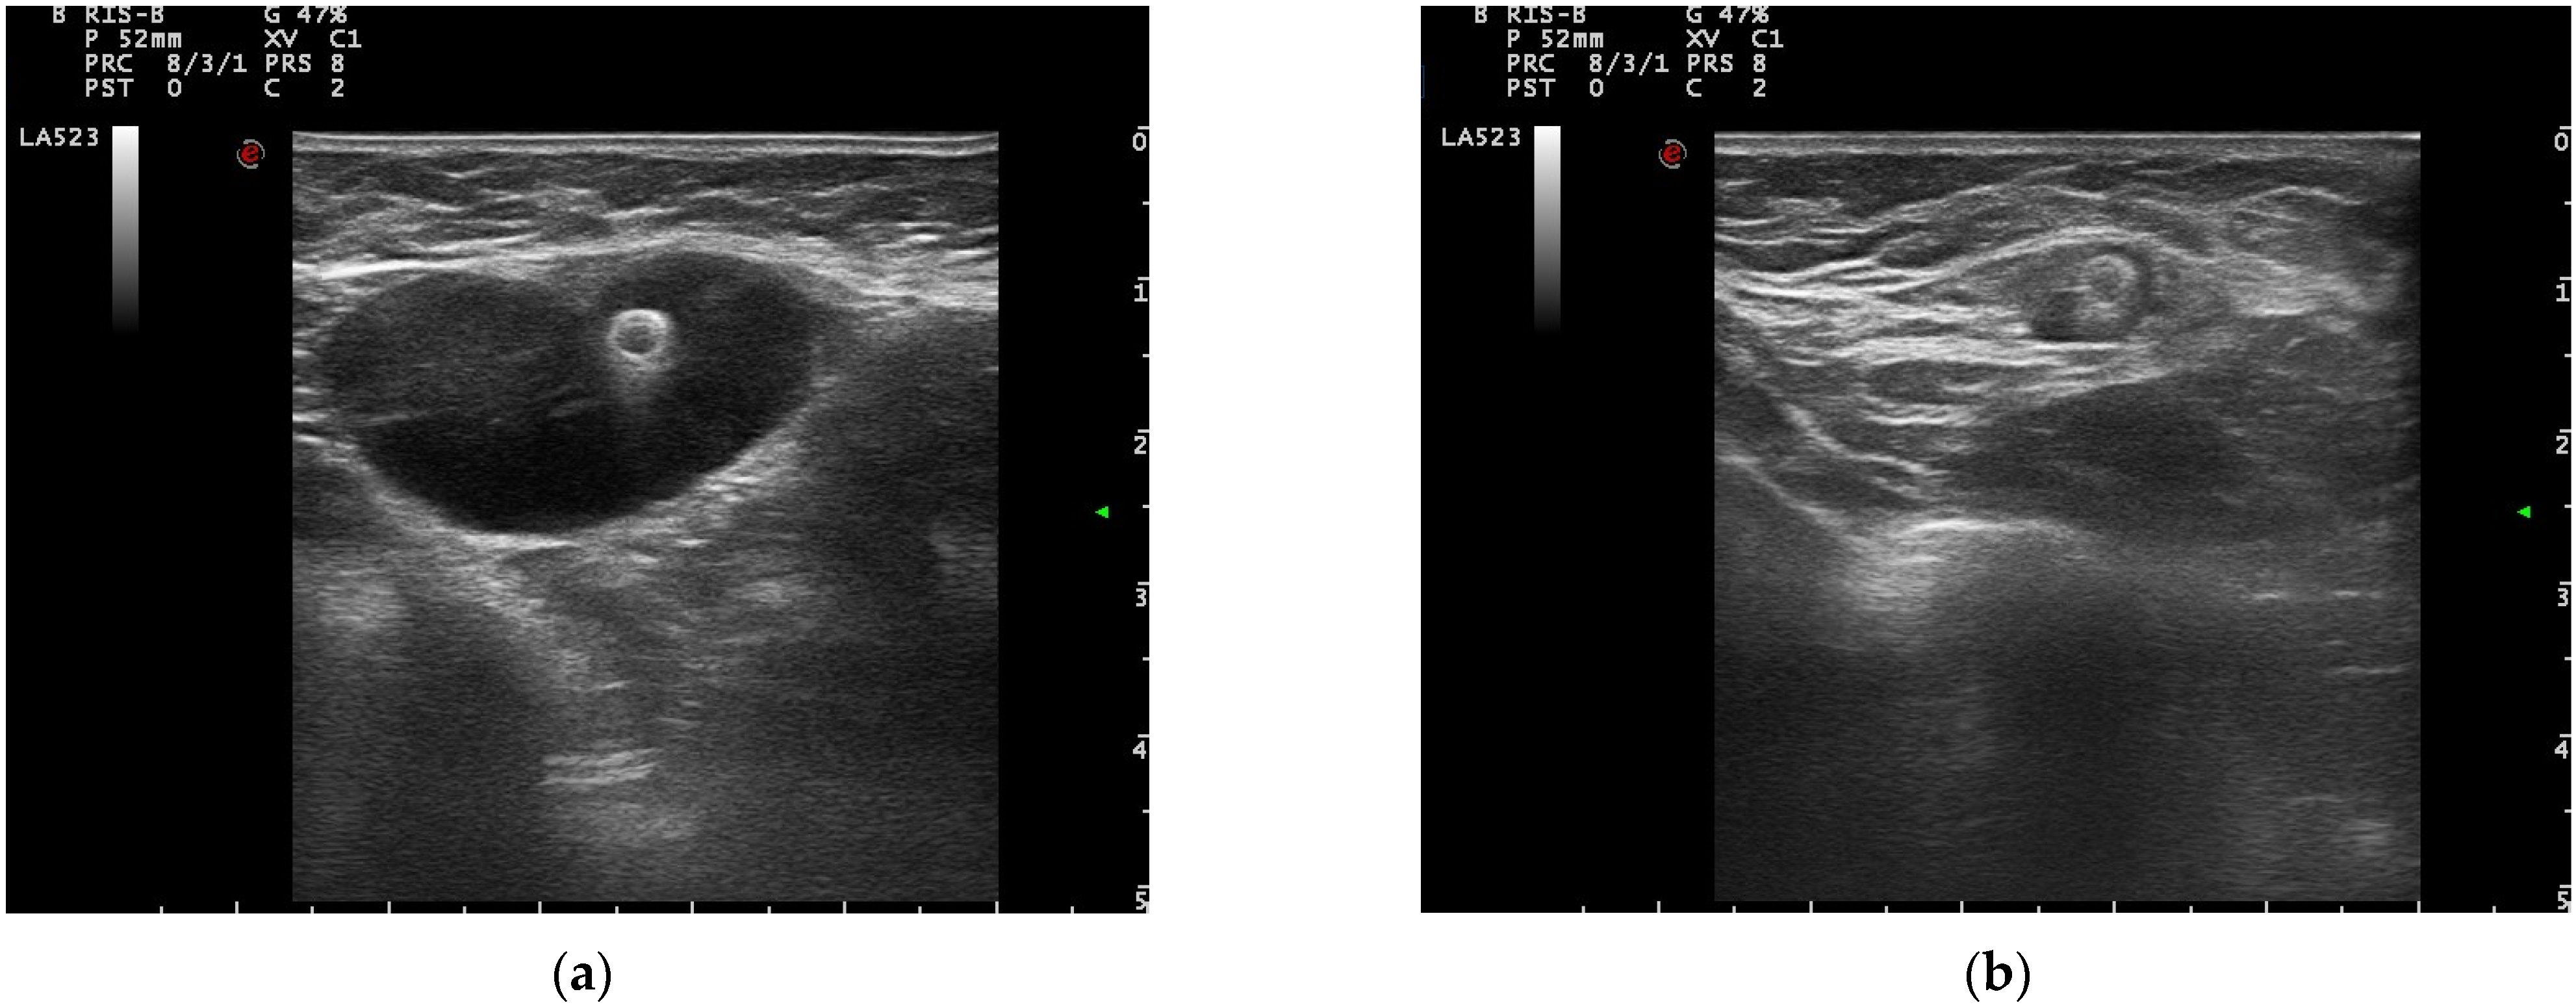

3.2. Pre-Operative Clip Visibility, Localization, and Surgical Management

4.2. Clip Positioning and Visibility